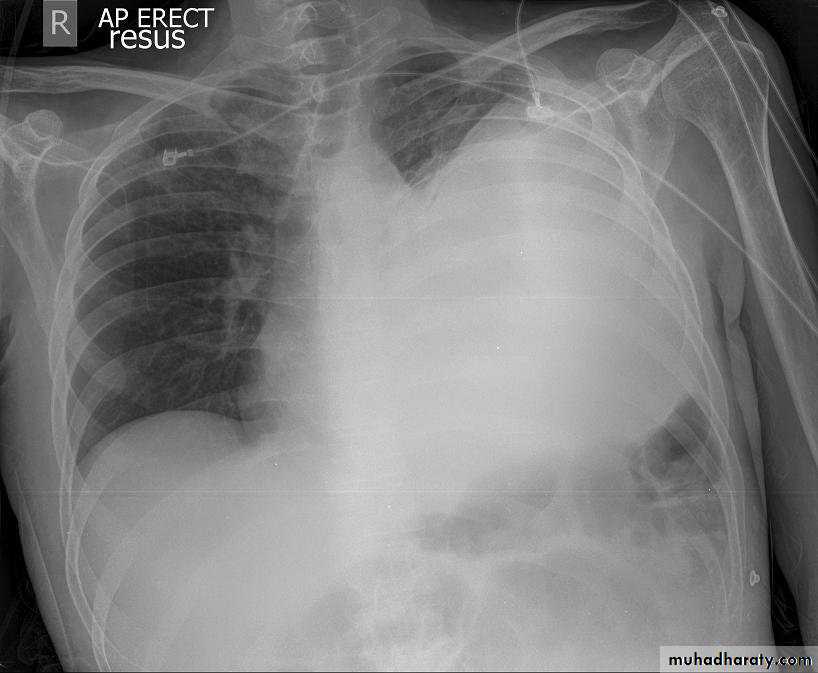

1-CXR:

PA and lateral views show effusion, air fluid level

CXR : Air fluid level is only seen in upright film